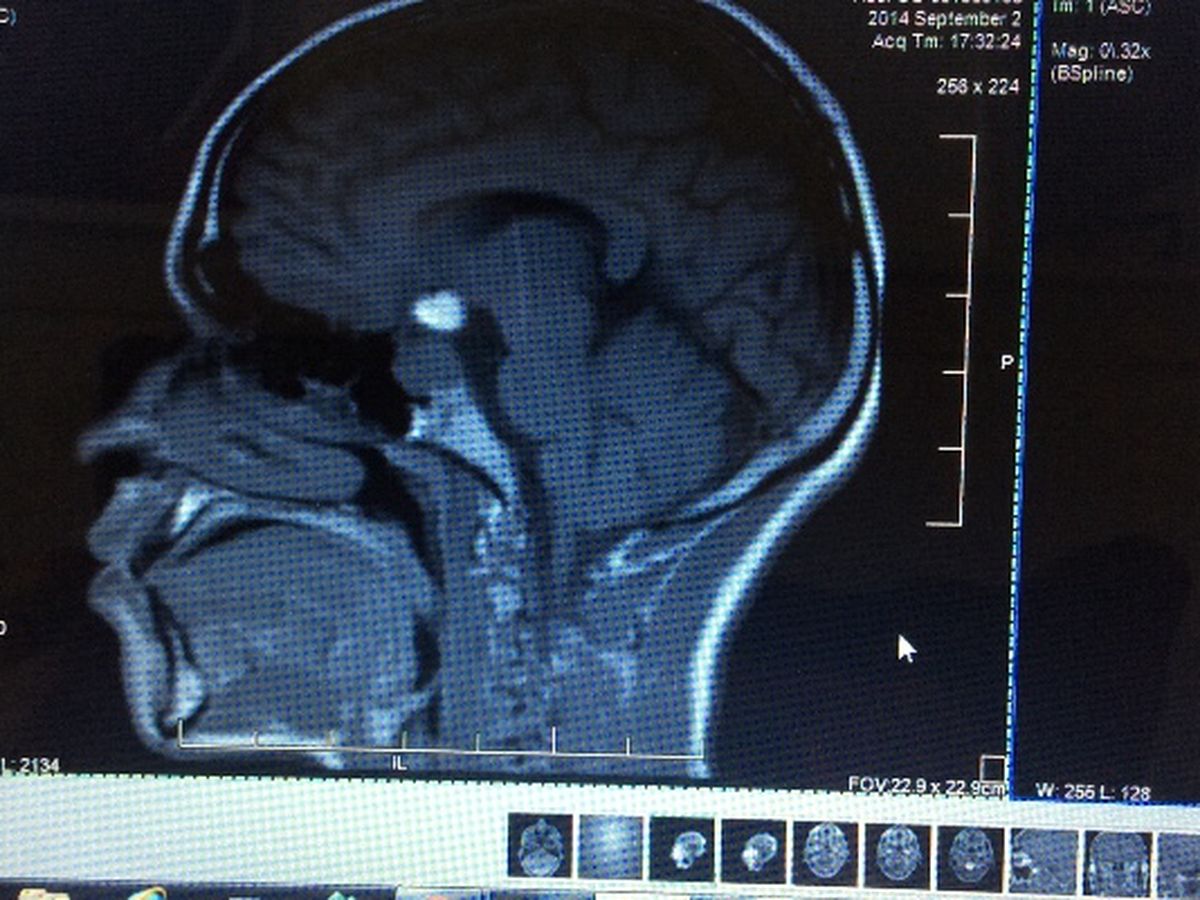

Before being diagnosed with a Pituitary Tumor, Luis was going to college at Florida Technical College, and used to play basketball at St.Cloud High School. Luis and his family need help from friends, family, and anyone else who would like to donate money towards medical treatment, medications, transportation, and for medical bills. Luis has already turned 21 years old, therfore, he no longer has medical insurance to contribute towards these items. He most take the medication in order to make the tumor shrink, to have surgery to remove the tumor. Also, luis is now having seizures and needs medications for it as well. For this reason we have set the goal for the amount of money we want to raise high, but any amount donated will be greatly appreciated.

Antes de haberme diagnosticado con un Tumor Pituitaria era un joven normal que cursaba enel Florida Technical College , antes en la escuela Superio de St Cloud jugaba enel equipo de Baloncesto. Necesitamos su ayuda para la deuda ya de 500,000 en hospitales y para medicamentos, medicos, transportacion, ect. Ya que cumpli 21 años no tengo seguro medico. Les agradezco su ayuda anticipadas de todo corazon.